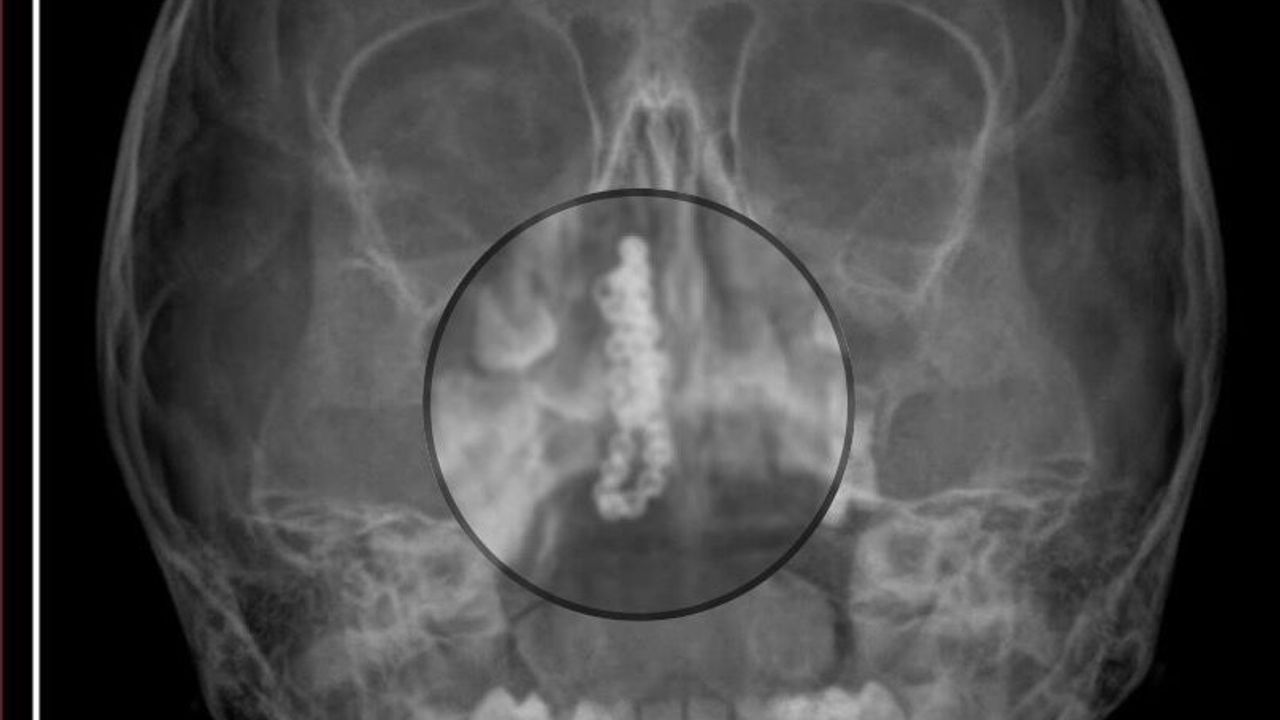

Kentte yaşayan Gökhan-Nalan Tekin çifti, yaklaşık 4 ay önce şiddetli burun kanamasının yanı sıra akıntı şikayetleriyle kızları Polen'i, bir özel hastaneye götürdü. Burada röntgeni çekilip, tetkikleri tamamlanan küçük kıza, iddiaya göre enfeksiyon teşhisi konulup, ilaç verildi. Eve dönen aile, kanama ve akıntının geçmemesi üzerine bu kez Rize Devlet Hastanesi'ne giderek Kulak Burun Boğaz Polikliniği'ne başvurdu. Devlet hastanesindeki doktorun incelemesi ve kapsamlı röntgen çekilmesi sonrası Polen'in burnunda metal cisim olduğu fark edildi. 2 yıldır burunda kaldığı değerlendirilip, küçük top şeklinde tırnak makası zinciri olduğu belirlenen cisim, başarılı ameliyatla çıkarıldı. Bir süre tedavisi sürdürülen Polen, sağlığına kavuşunca taburcu edildi. Özel hastane yetkilileri, konuyla ilgili açıklama yapmazken; aile suç duyurusunda bulunacaklarını söyledi.

Kızının burnundan sürekli siyah renkte akıntı olduğunu anlatan Gökhan Tekin, 'Çocuğumun burnundan kanama ile sürekli siyah akıntı geliyordu. Özel hastaneye götürdüm. Özel hastanede film çekildi, hiçbir bulguya rastlanılmadığı söylendi. O siyah leke de enfeksiyona dayalı olan bir şey olduğu bize söylendi. Eve geldik, akıntı sürmesi üzerine bu kez devlet hastanesine başvurduk. Burunda metal zinciri fark ettiler. Böyle bir ihmalkarlık olabilir mi? Özel hastaneye gidiyoruz, paramızla rezil oluyoruz. Zincir, 2 yıldır burnunda ve devletimizin hastanesinde iyi bir doktorumuz zinciri ortaya çıkarıyor, kızım ölümden dönüyor. Ben sonuna kadar bu işin peşini bırakmayacağım. Sonuna kadar hukuk mücadelesi vereceğim. Bu da diğer hastalarımıza ibret olsun. İşte, bakın koca bir zincir. 'Bulguya rastlanılmadı' deniliyor' dedi.

Kızının ameliyat sonrası durumunun iyi olduğunu söyleyen Tekin, 'İnanır mısınız bize 'Evde soba mı yanıyor? Acaba kömür isten dolayı mıdır bu?' dendi. Böyle bir şey olabilir mi? Ameliyattan çıkan parmağım kadar zincir. Devlet hastanesindeki doktor da 'Bu nasıl gözden kaçılabilir? Böyle bir pozisyon nasıl görülmeyebilir?' yorumunda bulundu. Allah'a şükür olsun atlattık. Şu anda durumu, vaziyeti iyidir. Ben şuna inanıyorum doktor da bir şans işidir. Bakın paramızla özele gideriz ya hani bizde, daha iyi ilgilenirler. Oysa devlet hastanesindeki doktorumuz olayı meydana çıkardı' diye konuştu. (DHA)